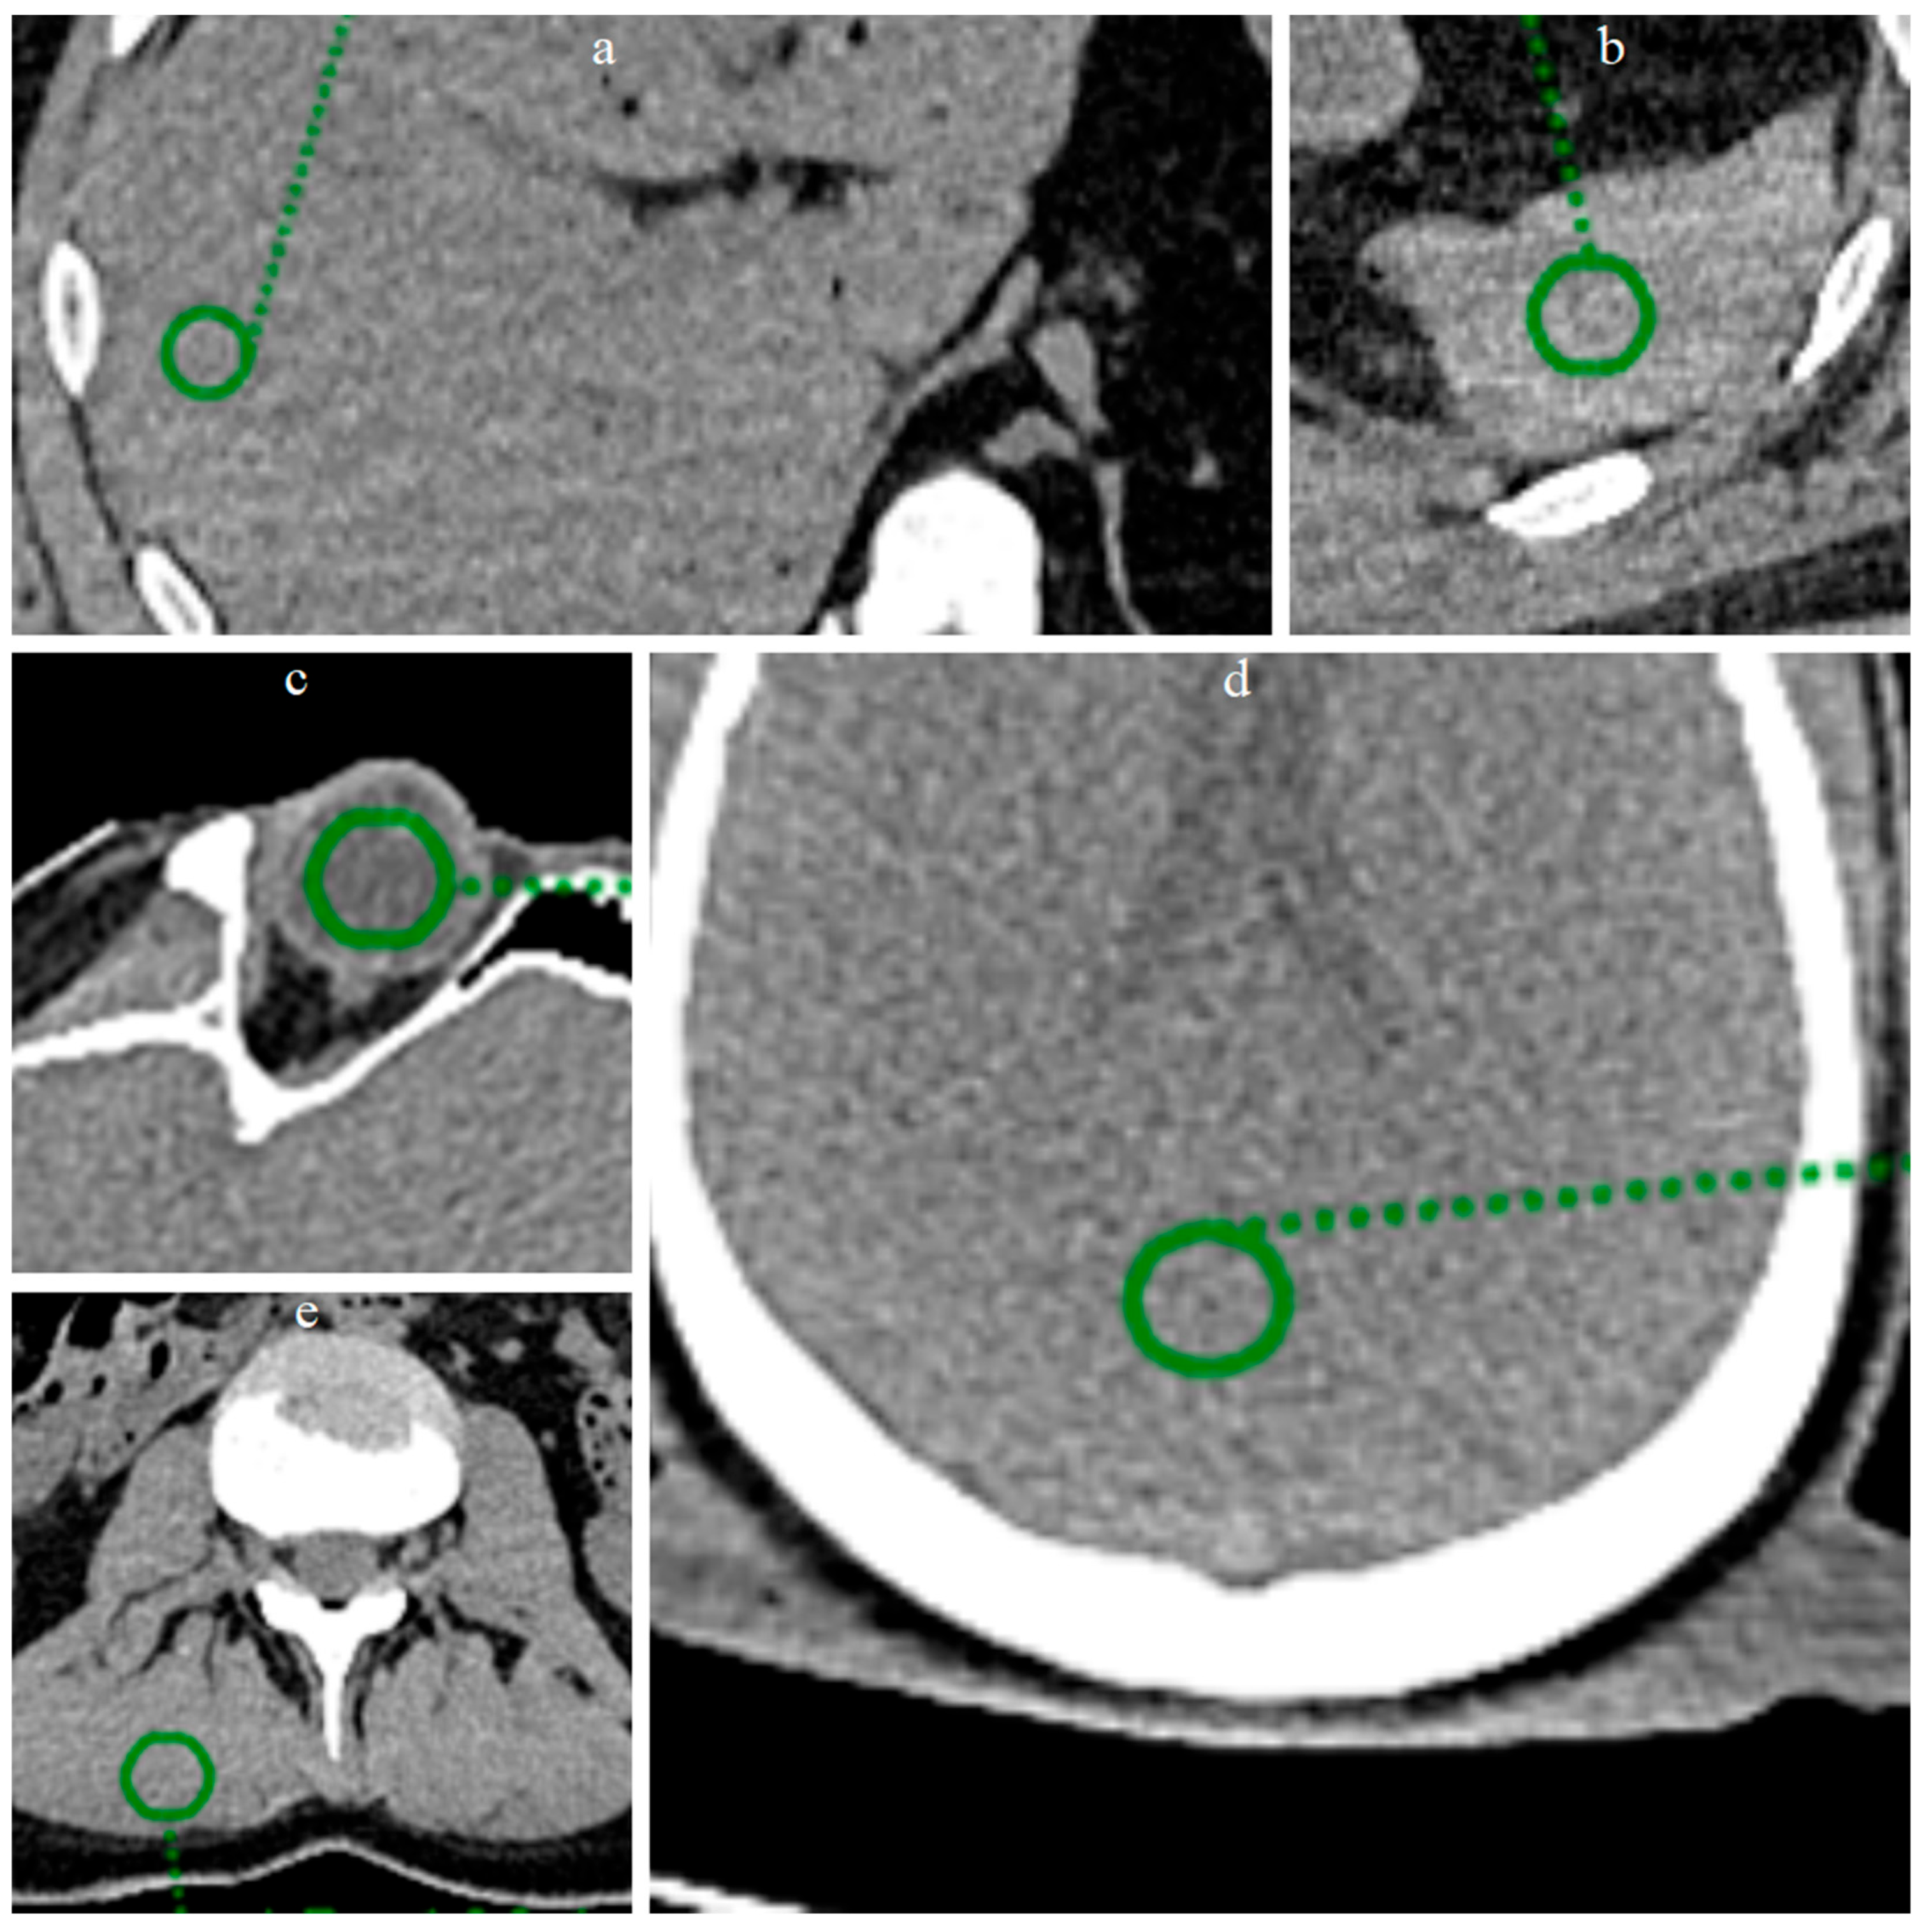

In the present study, a quantitative noise analysis was also performed by applying circular regions of interest (ROI) (radius 8 mm) at five anatomical locations (Figure 3): vitreous body, brain parenchyma, liver parenchyma, splenic parenchyma and paravertebral muscle. Within each ROI, the mean and standard deviation (SD) of the attenuation values (Hounsfield units) were calculated in order to characterize and compare the noise level before and after processing with ErisNet.

Figure 3.

ROI placement at five anatomical locations for quantitative analysis. Circular green ROIs with radius 8 mm were positioned on: (a) liver parenchyma, (b) splenic parenchyma, (c) vitreous body of the eye, (d) brain parenchyma, and (e) lumbar paravertebral muscle. These anatomical regions were selected to evaluate ErisNet performance across different tissue types and attenuation characteristics.

Circular ROI of radius 8 mm were placed on the images of the Test Set on the vitreous body (Figure 6), brain parenchyma, liver parenchyma, splenic parenchyma and paravertebral muscle, and the mean and SD of the mean values of Hounsfield Units (HU) were calculated for each ROI.

Figure 6.

Positioning of ROIs in five anatomical locations for quantitative analysis. Circular ROIs with a radius of 8 mm were placed on: (a,b) brain parenchyma, (c,d) vitreous body of the eye, (e,f) liver parenchyma, (g,h) lumbar paravertebral muscle, and (i,j) spleen parenchyma. For each anatomical location, the image on the left shows the low-dose acquisition, while the image on the right shows the corresponding result processed by ErisNet. These anatomical regions were selected to evaluate ErisNet’s performance on different tissue types and attenuation characteristics. The comparison demonstrates a consistent reduction in the standard deviation of Hounsfield units within the ROIs after processing with ErisNet (Table 4).